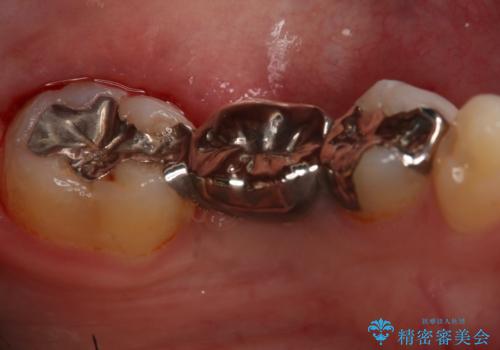

- 左下奥歯のブリッジのやり変え希望のため来院された患者様です。

支台歯部分はインレー形態でしたが強度や維持性を考慮しクラウン形態への変更を計画しました。